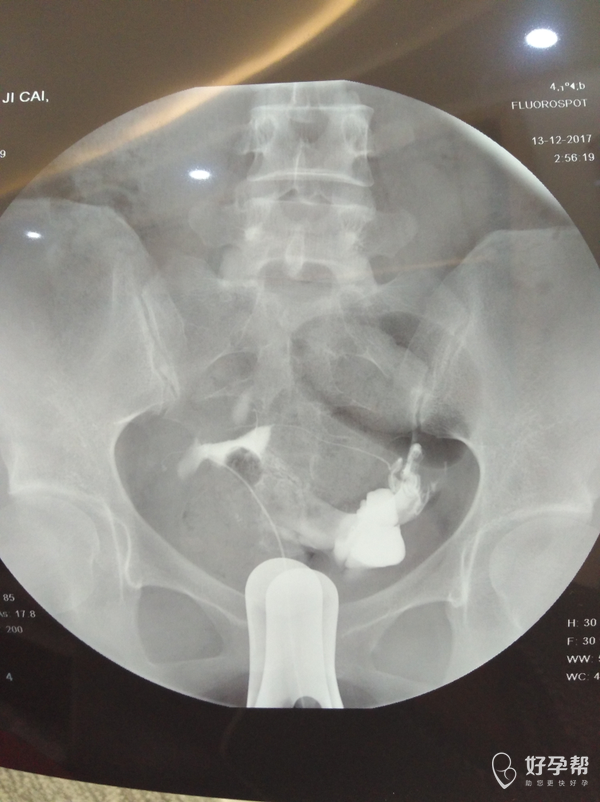

输卵管通而不畅应该怎么治疗

麻烦医生指点,输卵管通而不畅要怎么治疗?我的右侧输卵管部分切除,所有希望都寄托在这跟管上了,我不想试管,想自然怀孕,帮帮忙指点

,谢谢!从哪里看的出通而不畅的,也帮忙指点一下